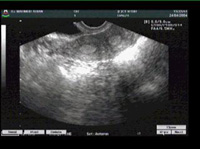

زنان سیگاری به سرطان گردنه رحم مبتلا می شوند

اگر سيگاركشيدن همراه با وجود مقادير زيادي از ويروس پاپيلوماي انساني در گردن رحم باشد, خطر بروز سرطان و پيشرفت آن افزايش چشمگيري مي يابد.

پايگاه‌اينترنتي انجمن تحقيقات سرطان آمريكاباانتشارگزارش آورده است : اگر سيگاركشيدن همراه با وجود مقادير زيادي از ويروس پاپيلوماي انساني در گردن رحم باشد, خطر بروز سرطان و پيشرفت آن افزايش چشمگيري مي يابد.

به گفته محققان اين دو عامل موجب تقويت اثريكديگر مي شوند.

سرطان گردنه رحم يكي از سرطان هاي رايج در جهان محسوب مي شود و با آنكه روش هاي غربالگري مناسبي براي تشخيص اين بيماري در مراحل اوليه وجود دارد هنوز هم گروهي از بيماران در مراحلي مراجعه مي كنند كه ممكن است قابل درمان نباشند .